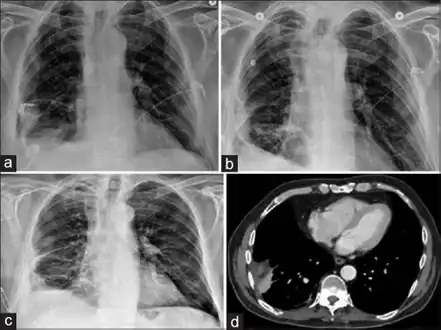

| Progression of empyema | |

Empyema -

Empyema with abscess